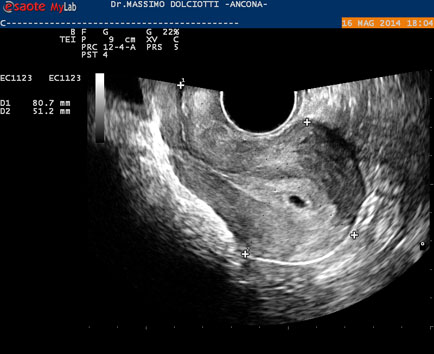

Data inserimento: 19 /05/2014Ecografia del: 16/05/2014 Strumento: Esaote MyLab 50 Gold - Responsabile Linea Cardio Esaote Regione Marche Dr. Franco Fabi Sonda: Endocavitaria Multifrequenza 4-8 MHz Età Paziente: F 27 anni Motivazione dell'esame: amenorrea. Beta HCG = 1.459 mUI/ml. Commento all'esame: le immagini ed il video documentano utero retroverso, con endometrio ispessito e presenza del sacco gestazionale delle dimensioni di 7,6 x 7,2 mm. All'ovaio destro presenza di corpo luteo gravidico con vascolarizzazione aumentata. Conclusioni: gravidanza alla quarta settimana di gestazione (Pregnancy at the fourth week of gestation). Potete esprimere le vostre osservazioni e commenti sul BLOG. Presentazione: Dr. Massimo Dolciotti - Ancona Elaborazione digitale: Andrea Dini - Ancona